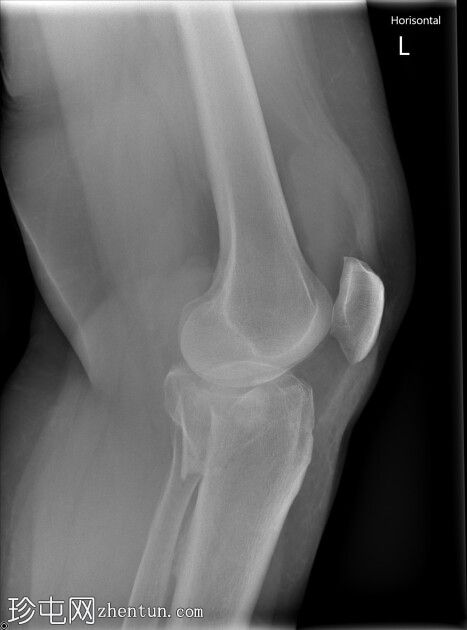

左膝X光片

X光片

侧面

胫骨近端内侧骨折,伴有隆起处凹陷和外翻。

Schatzker IV型。左胫骨近端。